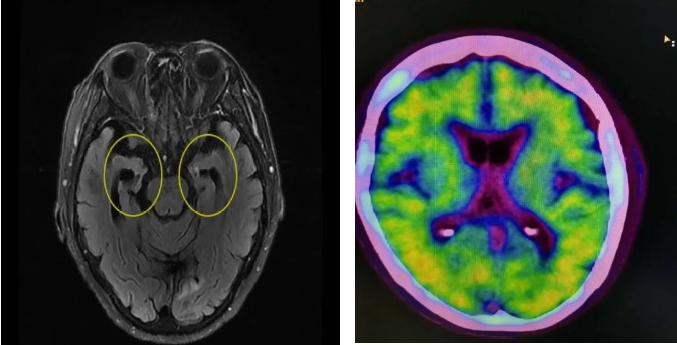

阿尔茨海默病不是“老糊涂”,家人正在被疾病悄然吞噬,亲人却往往忽略了早期征兆,无数患者因此错过最佳诊疗时机。许多被耽误的阿尔茨海默病患者来问诊时,病情已经发展到中重度。患者自己痛苦的同时,也给家属们带来极其沉重的经济心理双重压力。

阿尔茨海默病的早期征兆通常体现在3方面,分别是:认知出现障碍、日常生活能力下降、行为改变。每方面又各有3种常见表现。家中如有65岁以上老人,一旦出现下列表现,务必要考虑早期阿尔茨海默病的可能,及时就诊!